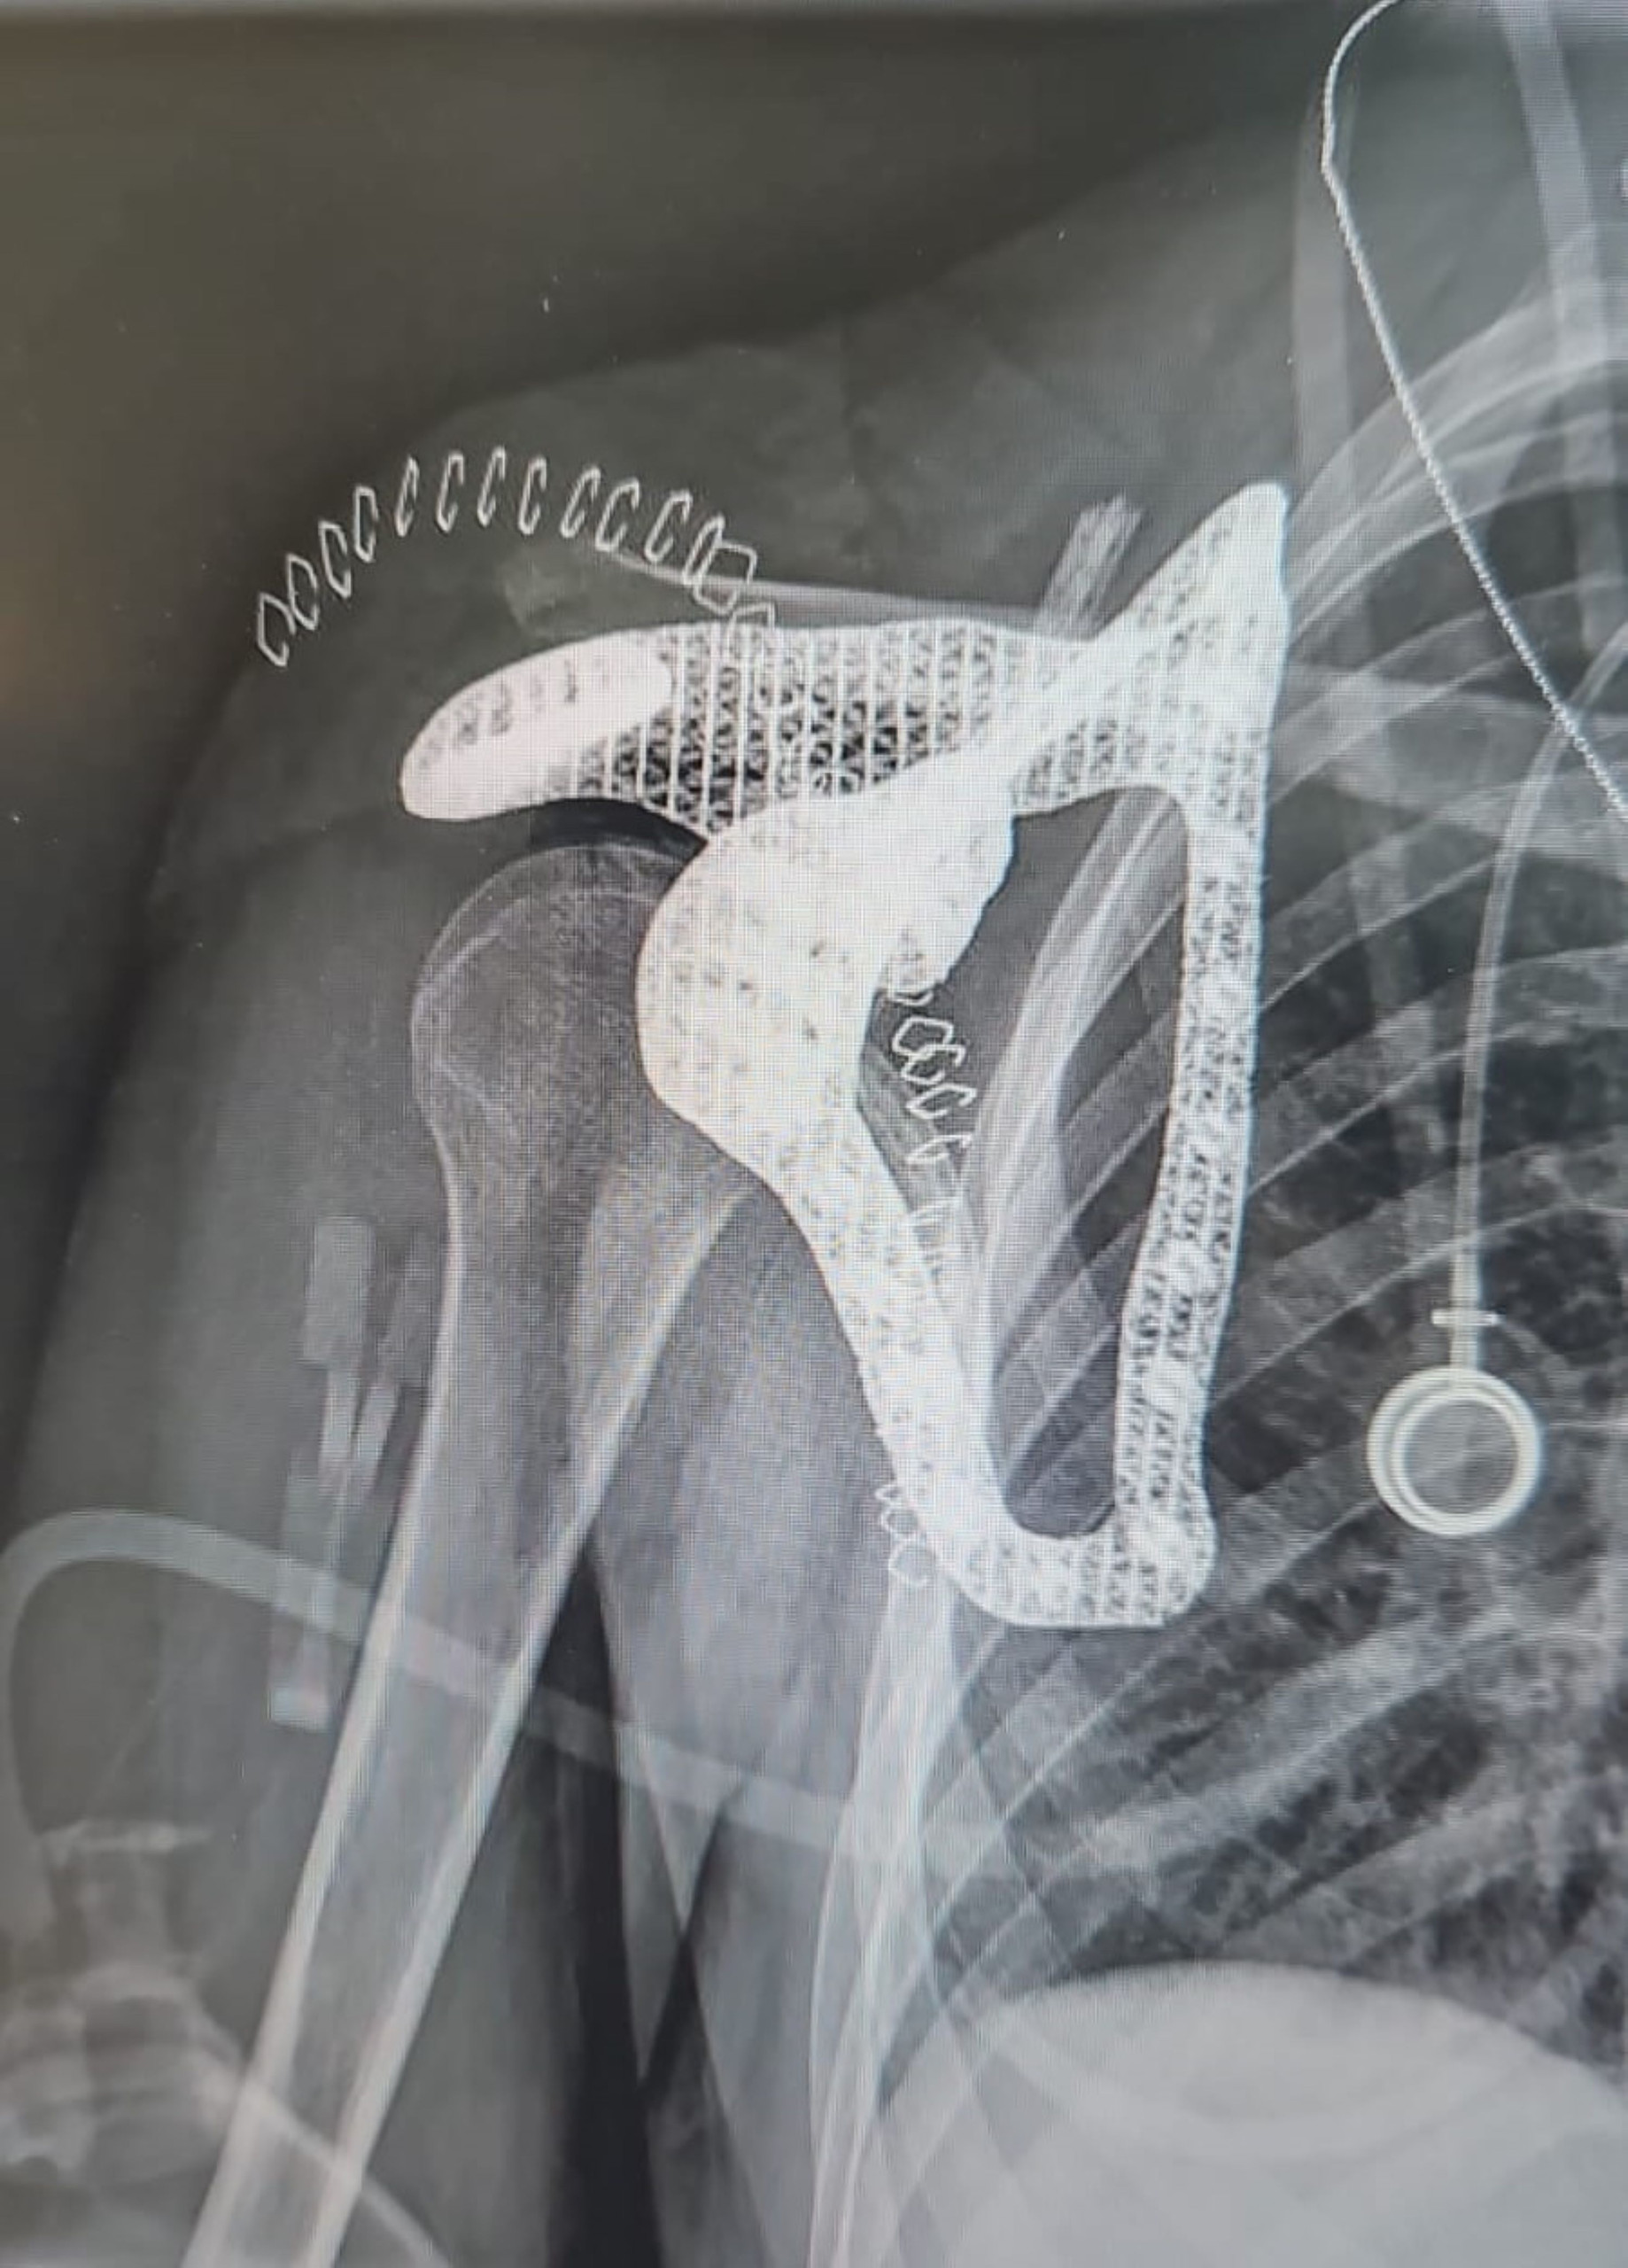

Personalisierte Medizin: Röntgenbild des Scapula-Implantats.

Röntgen-Aufnahme nach der Operation.

(Bild: Tel Aviv Medical Center)